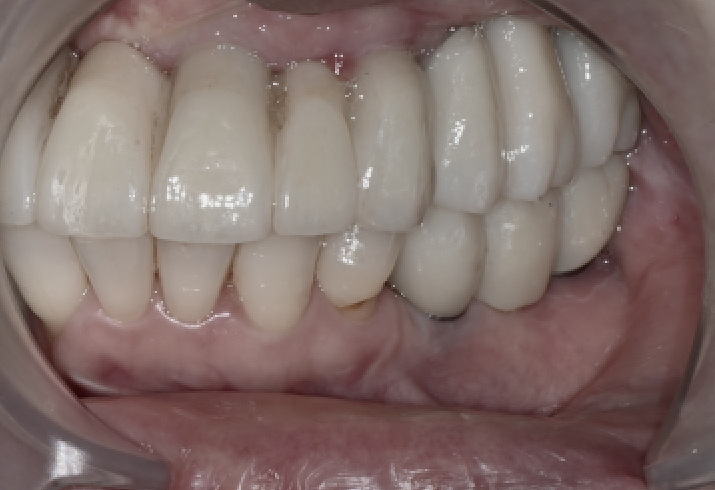

Final zirconia prosthesis placement

After sufficient adjustment,

we placed the final zirconia prosthesis.

It was designed to flow naturally from the front tooth line to the molar line,

and

we carefully adjusted the bite so that chewing force would not be concentrated on one side.

During this process, the patient said

that "the chewing force feels balanced overall."

3-month check after placement

Full-mouth implant surgery

When the patient returned 3 months later,

the implants, prostheses, and gums were all in a stable condition.

There was a feeling that the left side was chewing a little less,

so we made a very slight adjustment to the occlusal surface,

and after that, the patient has been using them comfortably.